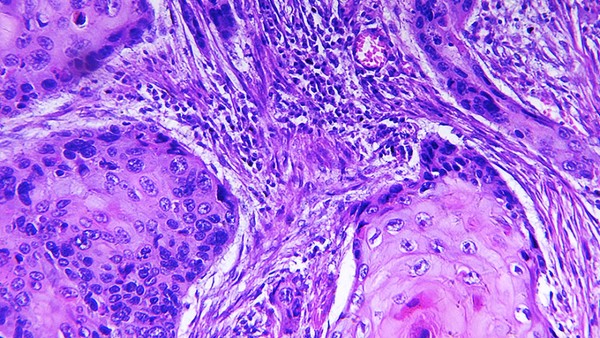

西安杨森是强生的制药子公司,也是改革开放以来最早进入中国的制药公司之一,公司业务包括生产和销售高质量的药品,产品主要涉及胃肠病学、神经精神学、变态反应学、疼痛管理学、抗感染、生物制剂和肿瘤等领域。